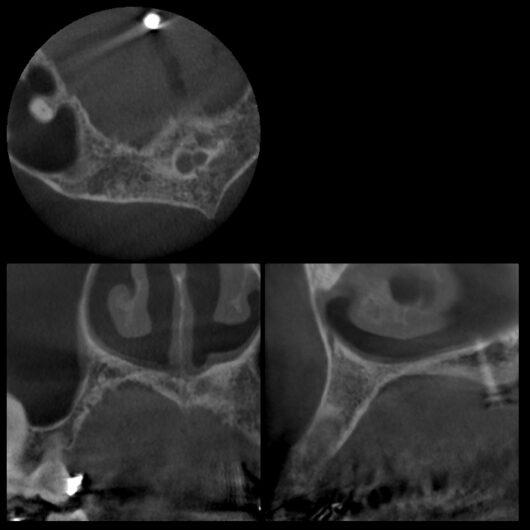

初診時レントゲン、CT

膿がおおきい

「前歯の違和感」という主訴に対して、まずは客観的な評価が必要です。今回、以下の検査を実施しました:

- デンタルレントゲン撮影

- CT撮影

検査の結果、インプラント周囲の骨の状態、インプラント体の位置、周囲組織の状態など、すべてにおいて問題は認められませんでした。これは、8年間適切にメインテナンスを継続してきた成果と言えるでしょう。